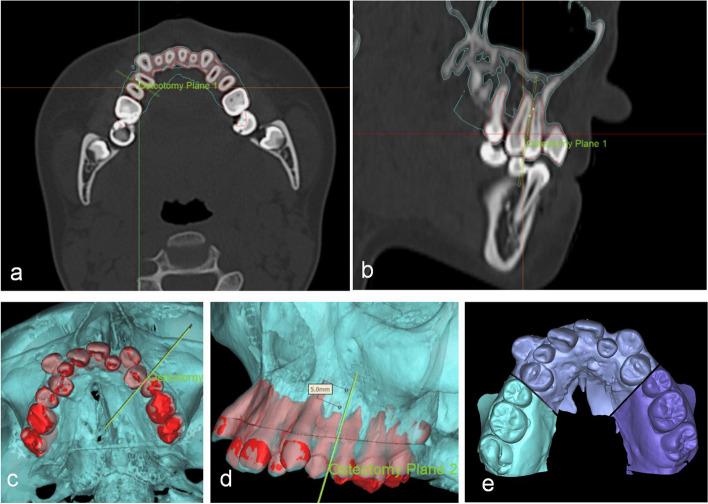

This study evaluates a three-dimensional (3D) visualisation design combined with customized surgical guides to assist anterior maxillary segmental distraction osteogenesis (AMSDO) in correcting maxillary hypoplasia in adolescents with cleft lip and palate (CLP), focusing on treatment outcomes, satisfaction and the validity of 3D planning.

This retrospective cohort study was conducted at a single hospital in China. Between January 2020 and December 2023, 12 adolescents with CLP with maxillary hypoplasia were included. An advanced 3D simulation was used to convey the treatment strategy to the patients and their families. A customized surgical guide and distraction osteogenesis device were designed. Cephalometric analysis evaluated AMSDO changes and long-term stability. Patient satisfaction was assessed. The Chinese version of the Child Oral Health Impact Profile was used to evaluate the children's oral health-related quality of life before and after treatment. The postoperative outcomes were compared with the planned outcomes by superimposing the actual postoperative data onto the simulated soft tissue models and calculating the linear and angular differences between them.

One patient experienced postoperative gingivitis, yielding an 8.33% complication rate. Most patients (83.33%) were highly satisfied with the target position, with the rest content. Cephalometric analysis showed significant improvements in various indices post-traction. Quality-of-life scores significantly improved post-treatment. The discrepancies in facial soft tissue between the simulated and actual results were within clinically satisfactory ranges.

Digitally designed surgical guides effectively treat maxillary hypoplasia in adolescents with CLP, ensuring stability, reducing complications, reducing dependency on operator experience, and enhancing satisfaction and health outcomes. Although the simulated results were clinically acceptable, it is important to inform patients of potential variations in the predicted soft tissue.